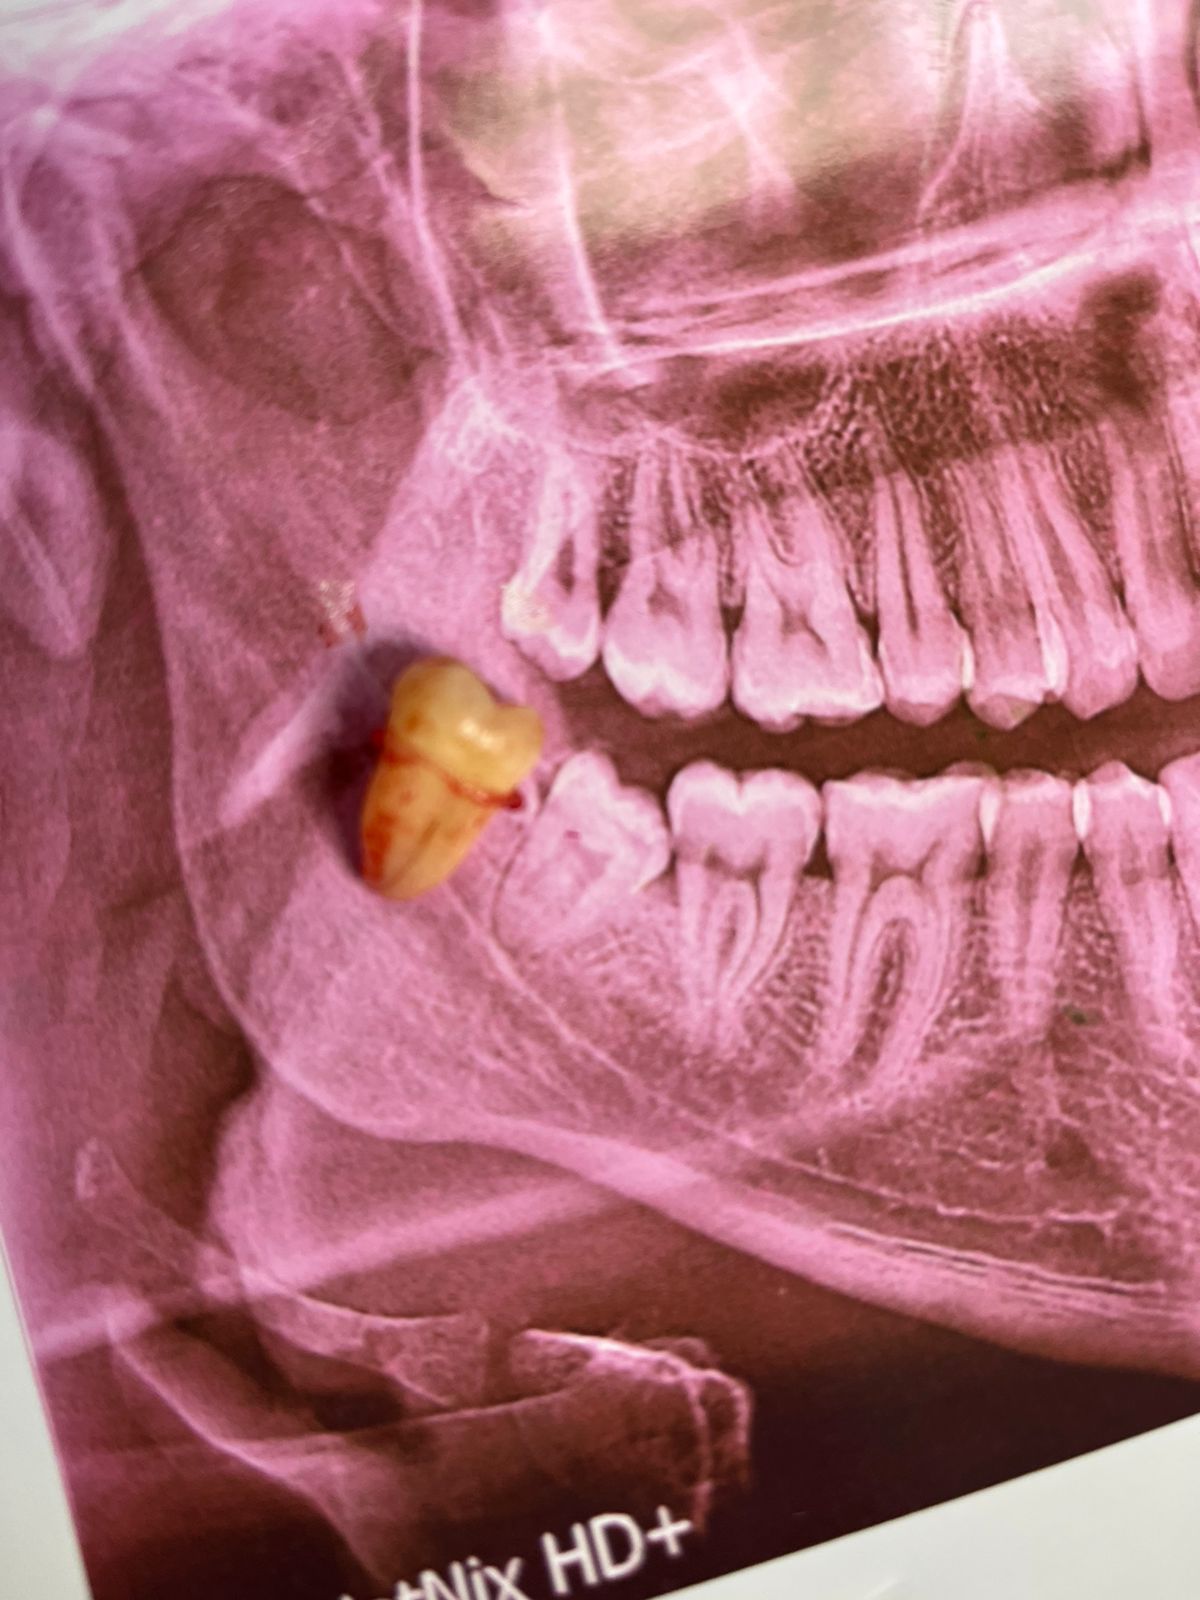

I started my internship at the maxillofacial surgery department at Al-Shifa Hospital, assisting in a few surgeries. However, the war began, bringing immense suffering and a series of tragic events and circumstances. To salvage what was left of my future and dreams, I decided to go to Egypt. My family remains in Gaza, enduring random bombings, killings, hunger, and displacement. While I managed to survive, I feel like I didn’t truly survive. I constantly worry about my family and the dire conditions they are facing. I hope God will protect them and bring an end to this genocide and brutal war.